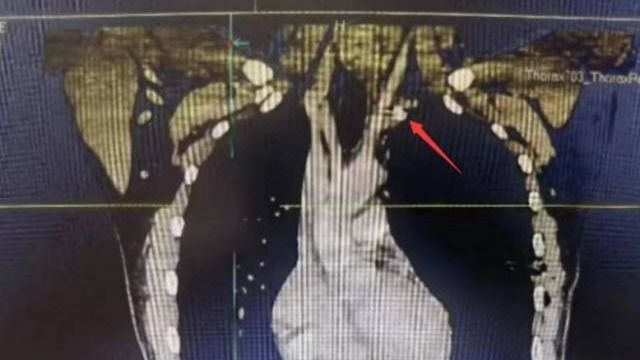

近日,中大五院胸外科成功为一名“熊猫”血型(B型Rh阴性)的左颈动脉外伤合并气胸的患者实施手术,取出一枚嵌插于左颈总动脉根部的金属异物,并修复了患者血管破口,避免大出血。原来,23岁的徐先生被高速旋转的金属模具碎片射中左侧颈根部,当即出现疼痛、呼吸困难,被紧急送到中大五院治疗。据医院外科主任兼胸外科主...